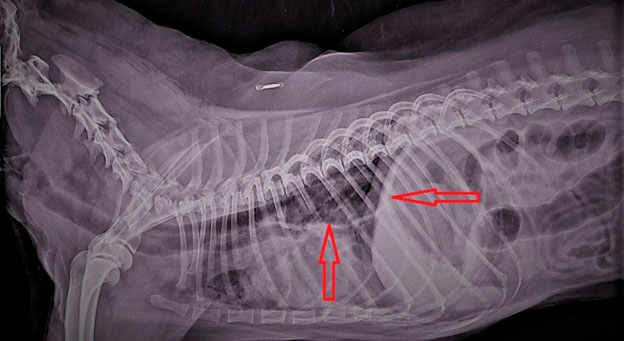

Рентгенодиагностика бронхопневмонии: Советы и примеры

Раздел: Альбом открытий